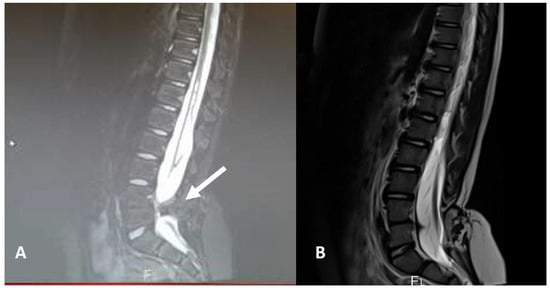

Figure 10. Preoperative (A) and postoperative (B) MR image of a completely removed transitional conus lipoma.

Premature disjunction leads to the formation of spinal cord lipomas. If the neuroectoderm separates from the cutaneous ectoderm too early, when the neural tube has not yet closed, this leads to infiltration of the still open neural tube by mesodermal tissue. The neural tube can therefore not close, and the placode (the exposed neural plate) is infiltrated by subcutaneous fatty tissue (Figure 9). This more or less thick lipomatous stalk can migrate from the subcutaneous tissue through the dysraphic bone and the dura into the intradural space. Lipomas of the spinal cord can be of the dorsal type (located on the dorsal side of the spinal cord and cranial to the still recognisable conus), of the transitional type (located on the dorsal side of the spinal cord and at the level of the no longer recognisable conus) or of the chaotic type (located on the dorsal and ventral side of the spinal cord, with an unrecognisable conus). Surgery for spinal cord lipomas, especially of the transitional and chaotic type, is complex and risky. Without surgery, 40–43% of these children develop tethered cord syndrome within 10 years [1,2,8,9]. At the same time, partial resection is also not recommended, as the results of subtotal removal are even worse than those of conservative treatment (follow-up with electromyography and urodynamic examinations), with 46% of these children developing tethered cord syndrome [8,9]. It is therefore necessary to completely remove the fatty tissue, undertake neurulation of the placode and create a wide dural sac with extensive duraplasty. Intraoperatively, it is often difficult to recognize the border between fatty and neural tissue, which is why neurophysiological monitoring is an absolute priority in these procedures. Using this technique, the risk of new neurological deficits is reduced to 0.8% over 10 years [8]. It is important to note that the risk of neurological deficits and the long-term prognosis vary, according to the type of lipoma and the position of the conus. Transitional lipomas with a low-lying conus are at high risk, compared to dorsal lipomas where the conus may be located at L1, L2 or L3 level. The higher risk carried by transitional and chaotic lipomas was confirmed also by our results: adult patients, in whom neurological deficits were statistically significantly more frequent than in children (p = 0.0098), also had a higher incidence of transitional and chaotic lipomas at diagnosis compared to children (57.1% vs. 44.4%). In our series, 15/22 (68.1%) conus lipomas were surgically treated (Figure 10). Our results confirm that conus lipoma surgery is safe, although the complexity of treatment of transitional and chaotic lipomas was evident, since permanent neurological deficits (one neurogenic bladder and three dermatomal sensorial deficits) were present exclusively in four of nine (44.4%) patients who had a transitional or chaotic lipoma (p = 0.0002).